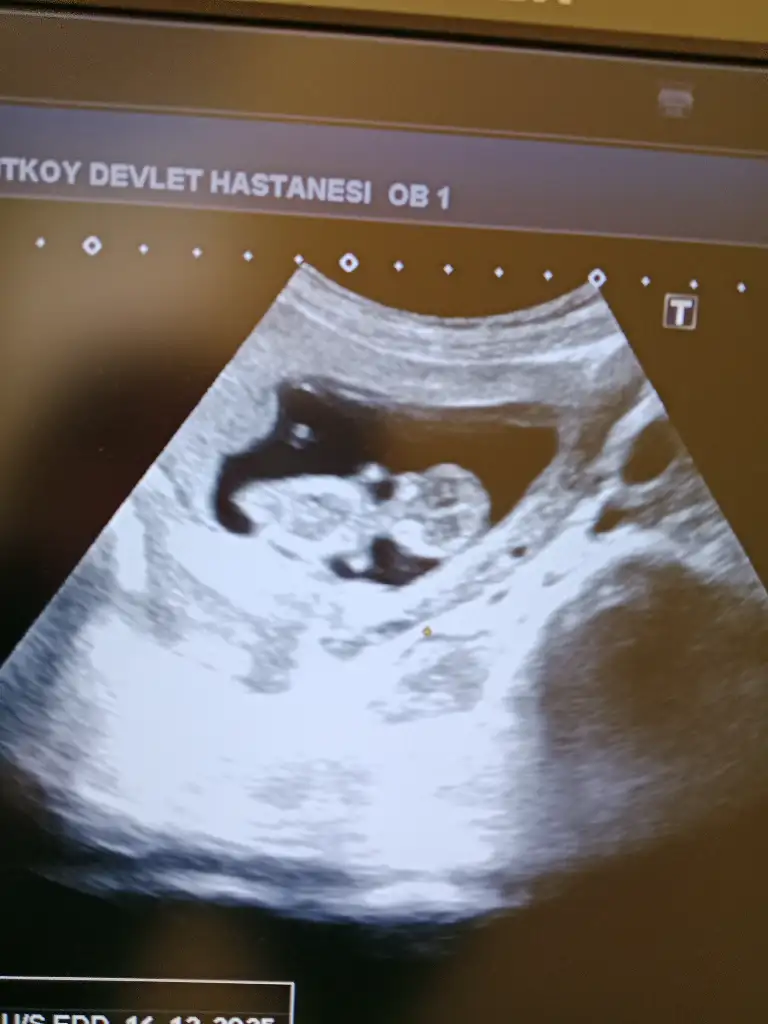

Pek anlaşılmıyor açıkçası. Bu arada kız görünüyordu bizim nub ama nipt testine göre erkekmiş öğrenmiş olduk 😅🌸 cinsiyet konusunda acele etmeyin değişebiliyor tavsiyem bir kere kız duyunca o kadar kendimi adapte ettim ki erkeği duyunca kal geldi haliyle 😅 önce sağlıklı olsunlar da tabii

Rica etsem bana da yorum yapar mısınız lütfen??🌸🌸